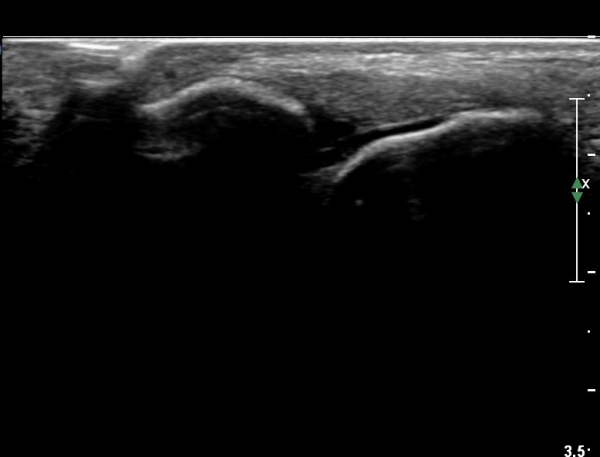

¹ß¸ñ ¾ÕÂÊ Á¾´Ü¸é°Ë»ç¿¡¼­ °üÀý³» ºÎÁ¾À» º¸ÀδÙ(»çÁø 1).

°üÀý³» ºÎÁ¾Àº ½É°¢ÇÑ ¼Õ»óÀ» ¾Ï½ÃÇÏ´Â ¼Ò°ßÀÌ´Ù.